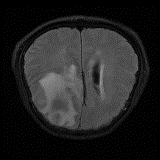

We obtain a subject-wise mean Dice score of 32.94% without any post-processing. By using a simple post-processing with erosion and dilation with filters, this number improves to 48.20% mean Dice score. In comparison, a similar study conducted by [3] consisting of a multitude of algorithms including AnoVAEGAN [4] and f-AnoGANS, obtained a best mean score of 27.8% Dice after post-processing by f-AnoGANS. Before post-processing the best method was Constrained AutoEncoder [8] with a score of 9.7% Dice. An exhaustive list is presented in Table 1. Figure 4 shows sample images of our results.

We obtain a subject-wise mean Dice score of 63.67% for the brain tumor segmentation. Utilizing a simple post-processing scheme of erosion and dilation with filter, we improve our mean Dice score to 68.01%. Figure 4 shows samples generated by our ASC-Net and Table 2 shows our before and after post-processing results. We attempted to apply f-AnoGANs [34] by following their online instructions and failed to generate good reconstructions as shown in Figure 5. The failure of AnoGANs in the reconstruction brings to light the issue with the regeneration based methods and the complexity and stability of GAN-based image reconstruction.

We obtain a slice-wise mean Dice score of 32.24% for this liver lesion segmentation, which improves to 50.23% by using a simple post processing scheme of erosion and dilation with filter. Sampled results are shown in Fig. 4. Compared with [42], which obtains a mean Dice score of 40.78% and a standard deviation of 0.43%, we improve the mean Dice score by almost 10%, but has a much larger standard deviation. Unlike [42], where the network is pre-trained on a artificial tumor dataset, and hence the pipeline customized for tumor segmentation, our method do not need such information beforehand. We notice that our standard deviation for BraTS dataset is similar to [27]. This is because novelty/anomaly detection algorithms without a pre-defined task would suffer from the co-morbidities issues discussed in Section 5.